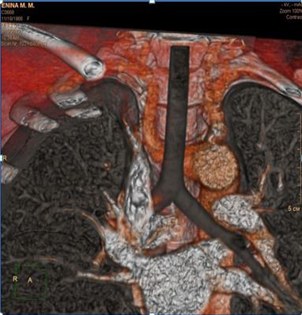

В послеоперационном периоде проводились дополнительные исследования – по данным ангиографии и компьютерной томографии подтверждено наличие сосудистой аномалии в виде a. lusoria. Послеоперационный период у больной протекал гладко, без осложнений. Фонация голосовых связок не была изменена. Проведенные дополнительные исследования подтвердили наличия a. lusoria. По данным МСКТ-ангиографии правая подключичная артерия (a. lusoria) отходит отдельным стволом позади и левее от места отхождения левой подключичной артерии, расположение ее предпозвоночное позади пищевода, отмечается сдавление пищевода (рис. 6 а, б, в).

Рис. 6. Результаты рентгенологического исследования: а – МСКТ расположения a. lusoria; б – компьютерная ангиография (вид спереди); в – компьютерная ангиография (вид сзади).